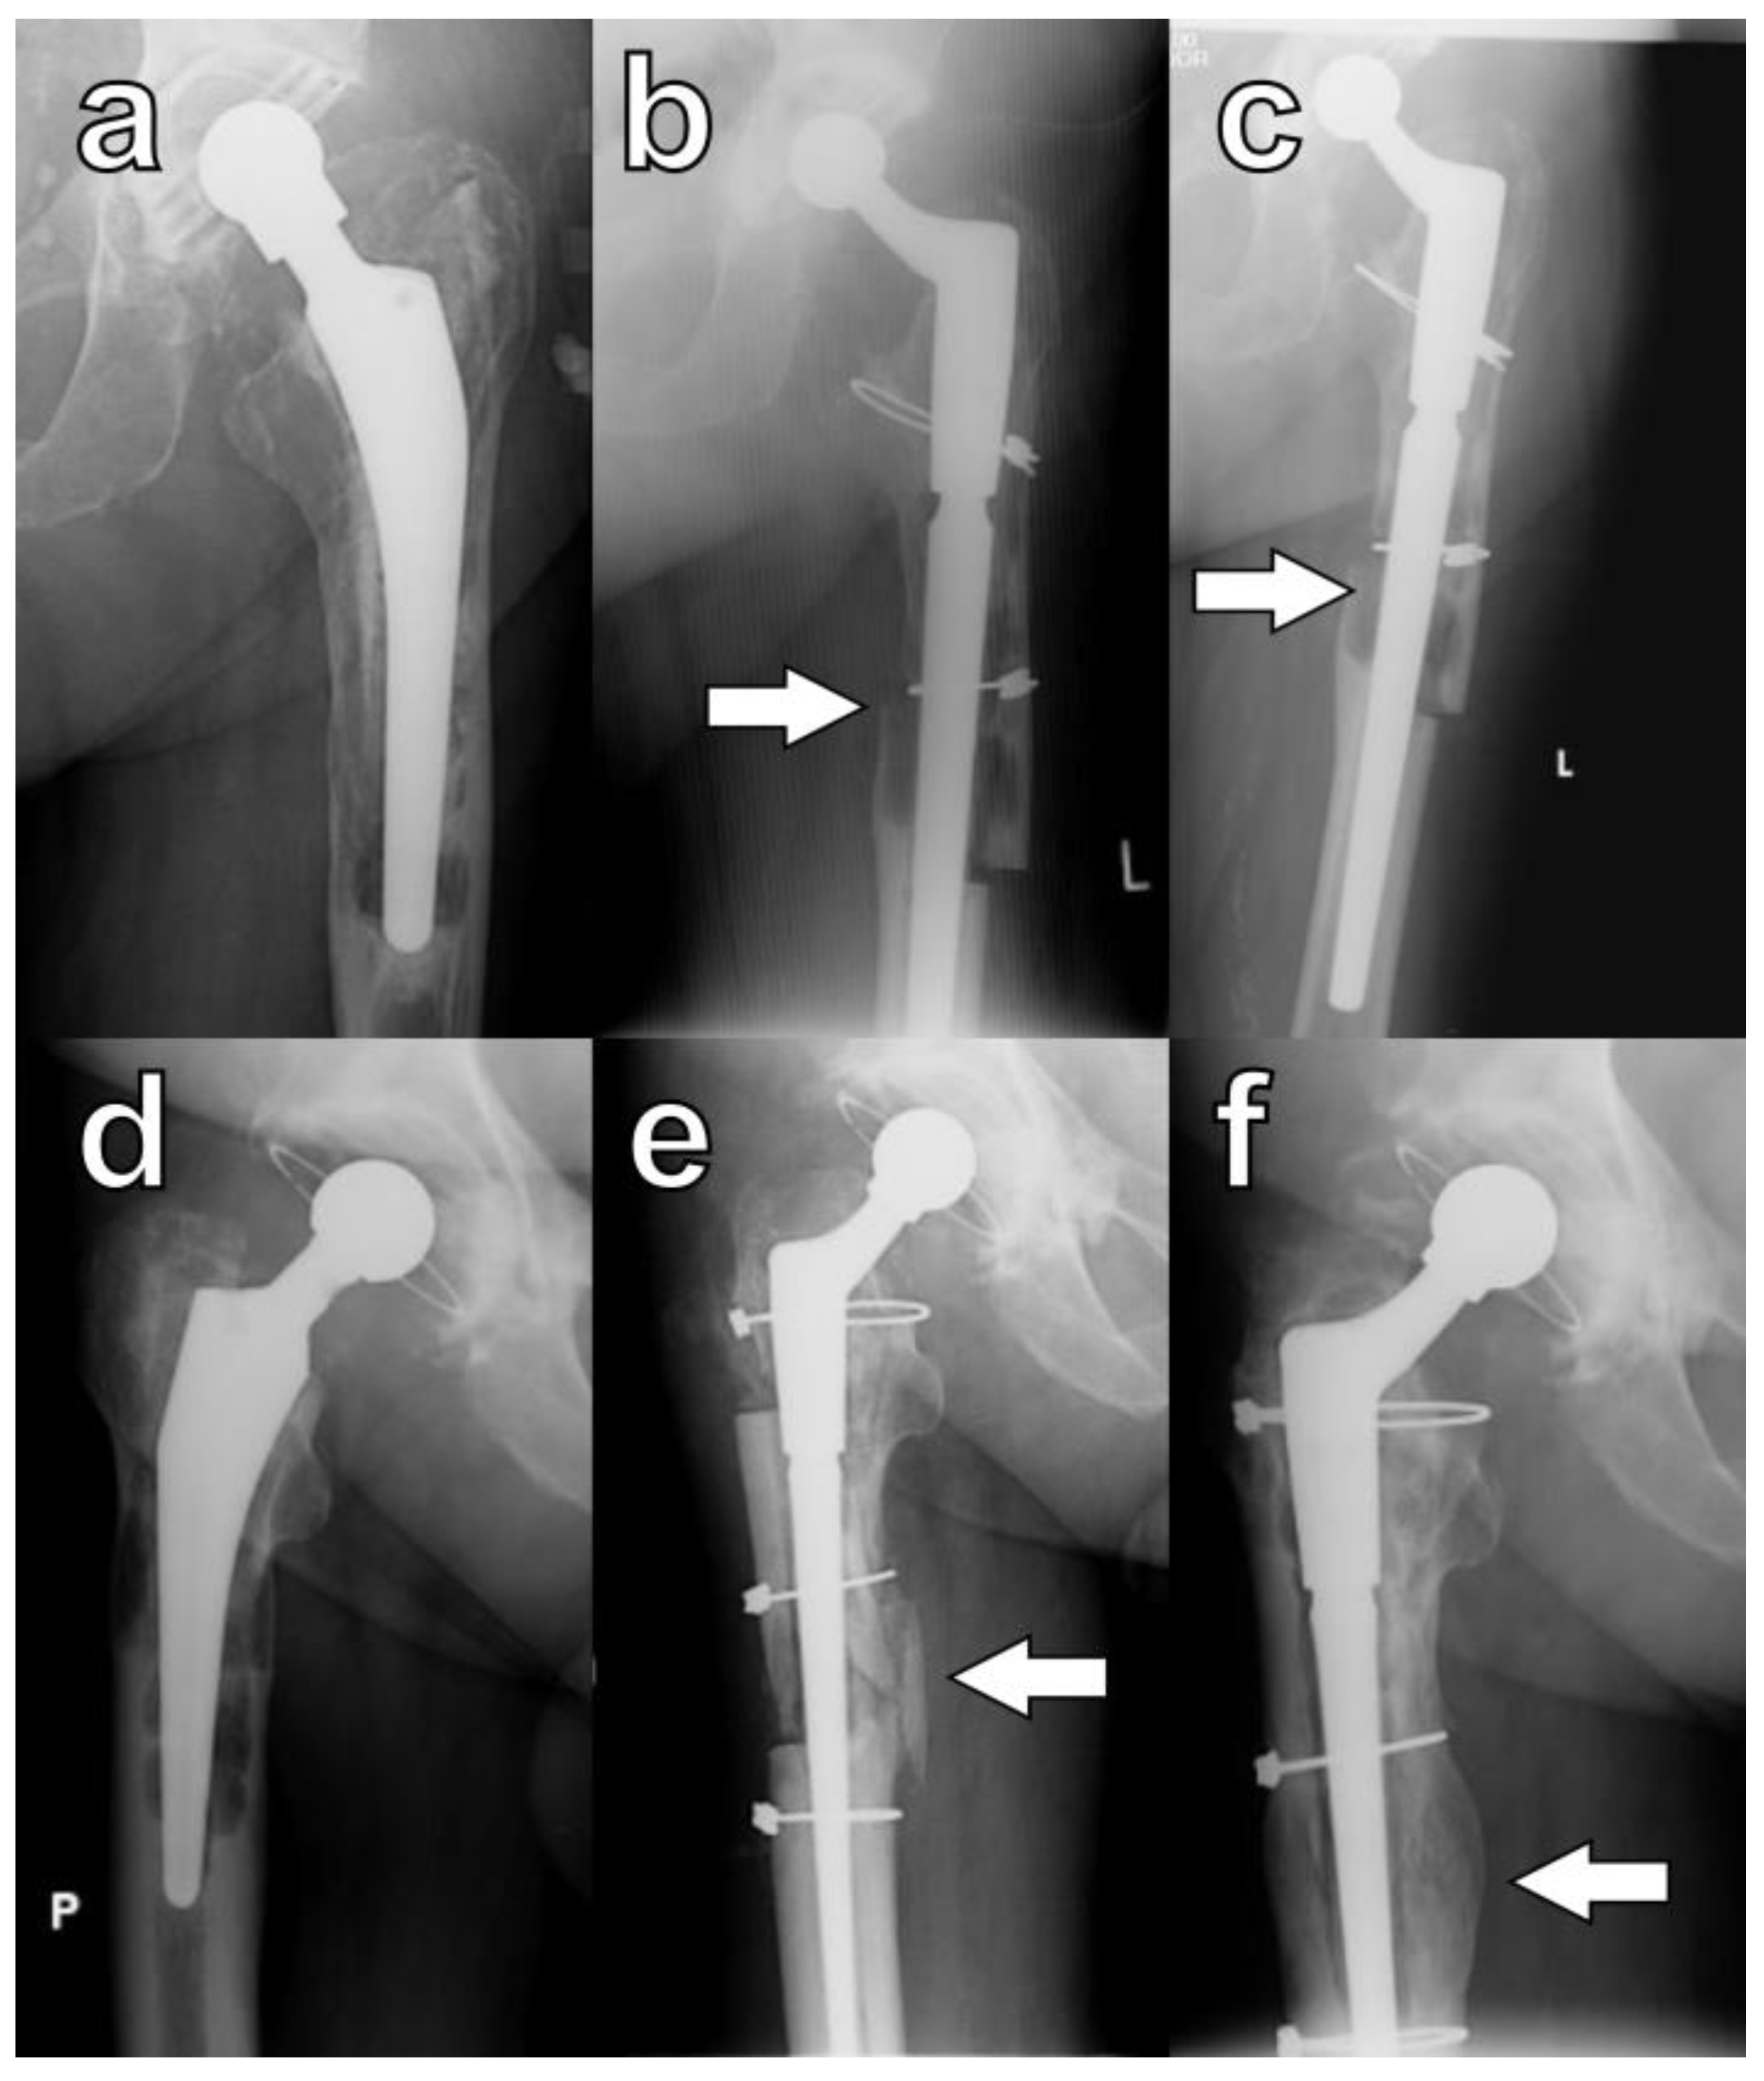

Radiographic union was defined by Abdel et al. as the presence of a callus bridging the osteotomy or the disappearance of the osteotomy line on orthogonal radiographs (Figure 4) [4].

Figure 4.

Healing of osteotomies as defined by Abdel et al. [4]: callus formation in serial radiographs of a patient K.W. taken (a) pre-op, (b) at six months, and (c) at eleven months; arrows indicate the formation of a callus at the osteotomy site. Bridging of the osteotomy site: serial radiographs of patient B.K. taken (d) pre-op, (e) at three months, and (f) at twelve months; arrows indicate direct bridging of the osteotomy site. P is an indicator for right side and L is an indicator for left side.

In this study, during the final evaluation, a lack of osteotomy union on any of the orthogonal radiographs was observed in four hips (9.5%). However, this phenomenon was not associated with decreased functional outcomes, and none of these patients required revision procedures (Figure 5a–c). In five hips, despite careful surgical techniques, large cortical bone fragments denuded of muscle were inadvertently broken off intraoperatively. Each of these devascularized fragments was subsequently attached to the femoral stem, and in all cases, osseointegration was observed (Figure 5d–f).

Figure 5.

Specific cases of ETO healing: lack of bone formation within the osteotomy (a) pre-op, (b) at six months, and (c) at twenty-four months. Osseointegration of a devascularized bone fragment: (d) pre-op, (e) at three months, and (f) at six months; arrows indicate osteotomy sites. P is right side, and L is left side.